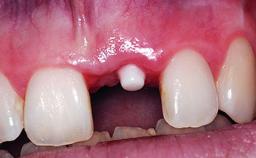

A 30-year-old patient presented at our clinic with a chief complaint of pain in her endodontically treated right maxillary central incisor (tooth 11) with a post-and-core and a fixed single crown. She had a very high lip line, a medium to thin soft-tissue phenotype, and a medium scalloped gingival contour. She also had high esthetic expectations because of her young age and beautiful smile. However, her expectations were realistic and she understood the risks of the treatment. At the initial clinical examination there was a slight mobility of tooth 11; no fistula was observed. The patient also had a single crown on the adjacent tooth 21. Both restorations were old and esthetically deficient. A digital periapical radiograph showed a very small periapical radiolucency, a thick intraradicular post, and no separation between root fragments.

Bone Augmentation Staged

Augmentation Materials Xenogenous|Membrane